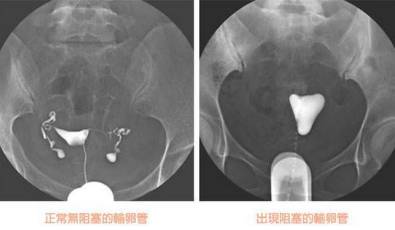

輸卵管造影檢查,精準(zhǔn)了解輸卵管病變情況

輸卵管造影是用來(lái)檢查女性輸卵管通暢與否的一種檢測(cè)方法。目前,輸卵管造影是臨床上應(yīng)用較為廣泛的方法之一。造影是通過(guò)導(dǎo)管經(jīng)陰道、宮頸、子宮腔直接插向子宮角的輸卵管開(kāi)口處,對(duì)著輸卵管推注造影劑而使輸卵管顯影,進(jìn)而了解輸卵管是否通暢、阻塞部位及宮腔形態(tài)的一種檢查方法。